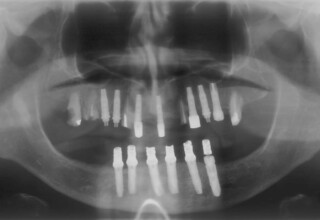

Lower jaw: extractions, direct implant placement and immediate loading (same day) with a transitional bridge.

Upper jaw: Sequential extractions, sequential implant placement and gradual incorporation in the temporary bridge so that the patient was never left without fixed teeth. The aim of the above approach was to have the patient in continuous functional and aesthetic reconstruction, without immediate loading due to anatomical restrictions. Old smiling photos of the patient were used because the natural shape of the teeth was completely lost due to repetitive prosthetic attempts. Tooth relationship and teeth-lip support was transferred to the temporary restorations. Two different transitional bridges were needed to fully estimate phonetics, mastication and esthetics. After the necessary adjustments were finalized, the temporary bridge was used as a guide for the permanent bridges.

Initial

Intermediate

Final